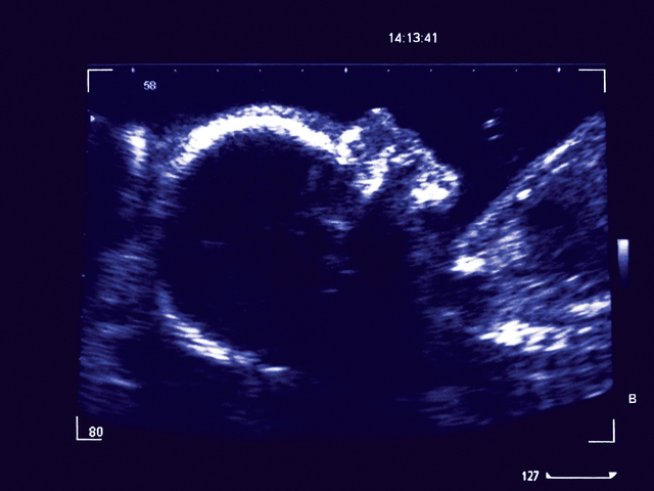

От момента на зачеването в утробата на жената се случват редица промени. Новият живот расте и се развива и прави изумителни неща. Доказано е, че бебето преди да се роди пишка, смуче си пръстчето и вижте още какво.

Първите усмивки на вашето бебче може да видите, ако наблюдаващият ви лекар ви направи 4D сканиране. Бебетата започват да се усмихват в утробата около 26-ата седмица от развитието си.